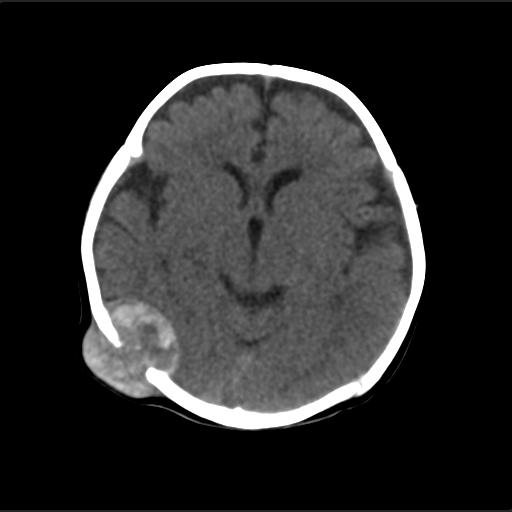

f2m出生已来可见右侧枕部见包块,质地软,无外伤史。包块处ct值16-67hu,大小约3.1x3.2cm左右。

局部颅骨破坏,并以破坏为中心的高密度肿块影,内示软骨影,考虑颅骨软骨瘤.

病灶位于颅缝区,向内外生长,边缘光整。考虑脑膜瘤

血肿机化可能性 比较大,伴双侧额颞顶部硬膜下积液。估计产伤引起